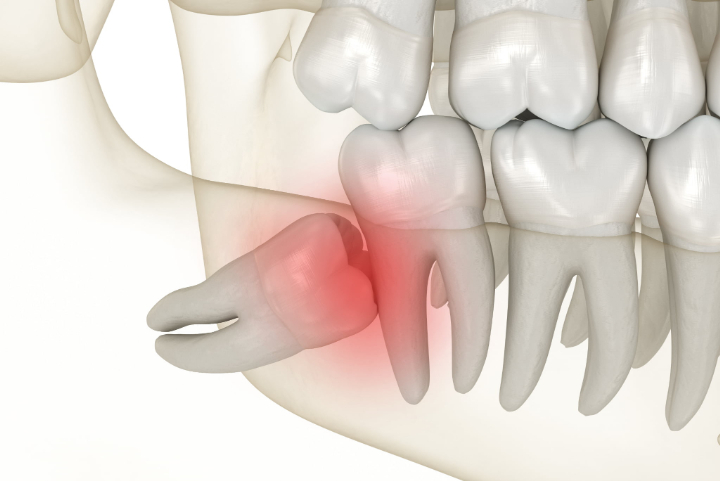

横向きや斜めに傾いた状態で生えるケースもあります。顎のスペースが不足していると、親知らずがまっすぐ生えてくることができず、手前の歯に向かって傾いた状態になります。

この場合、隣の歯との間に汚れが溜まりやすくなり、虫歯や歯ぐきの炎症の原因になることがあります。また、歯ぐきが部分的に覆ったままになることもあり、そのすき間に細菌が入り込みやすい状態になります。

特に歯の一部だけが見えている状態では、歯と歯ぐきの間にすき間ができやすく、そこに細菌が入り込むと炎症が起こる場合があります。この炎症は智歯周囲炎と呼ばれ、歯ぐきの腫れや痛み、口の開けづらさなどを引き起こすことがあります。

また、親知らずが斜めや横向きに位置している場合には、手前の歯を圧迫することで鈍い痛みや違和感につながることもあります。さらに、疲れや体調不良によって免疫力が低下しているときは、炎症が強く出やすい傾向があります。